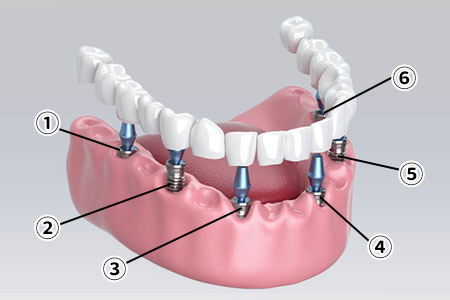

すべての歯を失った、総入れ歯が合わずにお悩みの方へ、従来は8~14本のインプラントが必要でしたが、オールオン4なら最小4本のインプラントで12本の噛める歯をしっかり支えられます。

骨の硬い部分を正確に狙い、角度や力を調整してインプラントを埋入。器具の長さや太さも最適化し、安定した咬合を実現します。オールオン4は高度な技術が必要なため、対応できる歯科医師や医院は限られています。

オールオン4とはたった4本のインプラントで12本の歯を保持する方法です。全ての歯を失ってしまった方、総入れ歯の方に行う治療法です。抜歯からインプラントの埋入、仮歯を入れるまでが1日でできます。

通常のインプラント治療は、部分的な歯の欠損を補う治療法が一般的です。顎の骨にインプラントを埋入し、骨としっかり結合するのを待って上部構造(被せ物)を装着します。オールオン4はこの治療法の応用編と言えるでしょう。

骨の弱い方や、骨が柔らかい方には、インプラント6本で歯を支えるオールオン6がお勧めです。

オールオン6とは、6本のインプラントで12本の歯を支える治療方法です。

この方法は、日本人のように顎の骨が比較的やわらかいケースで採用されることが多く、オールオン4との主な違いは、使用するインプラントの本数が4本か6本かという点にあります。

そのため、オールオン4を希望される患者さんでも、骨の状態によっては6本のインプラントで治療を行う方が、より安定して長く使用できる場合があります。